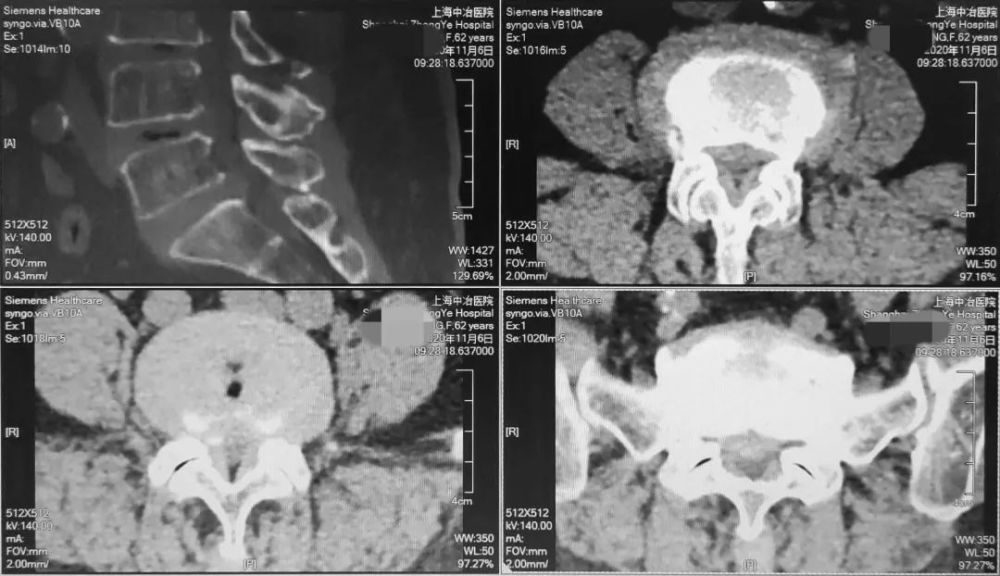

CT

CT可清楚地显示椎管横断面的骨性结构 , 对侧隐窝狭窄 , 黄韧带肥厚 , 椎间小关节病变及神经孔周围极外型推间盘突出的显示有独特的临床价值 。

文章插图